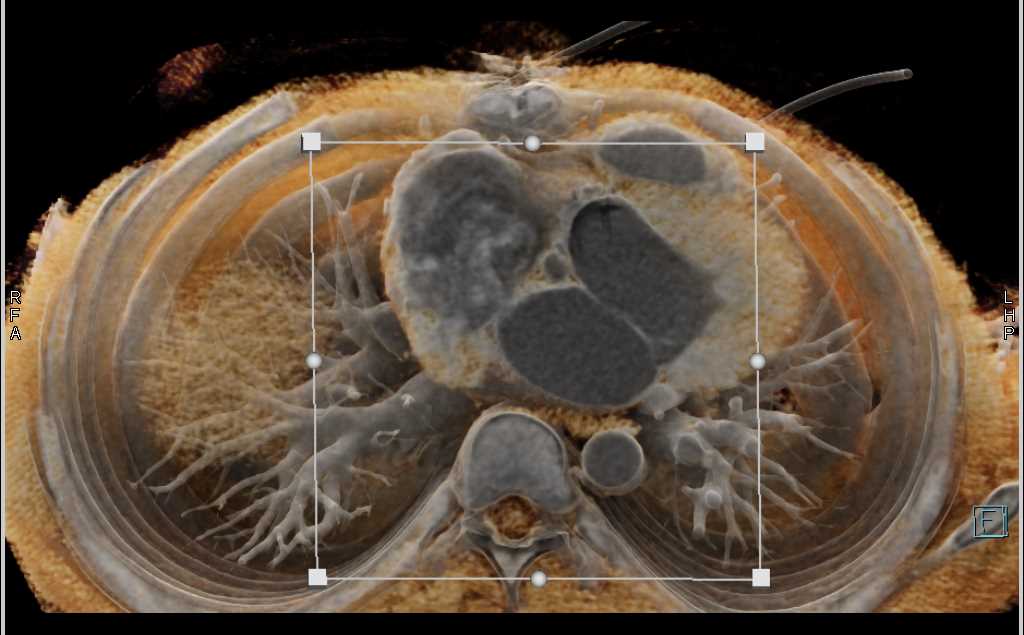

Aortic Valve Repair